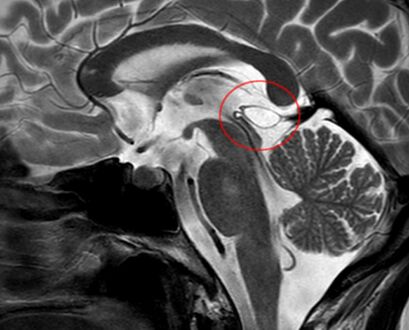

كيسة الغدة الصنوبرية

كيسة الغدة الصنوبرية pineal gland cyst هو تكيّس حميد (غير خبيث) في الغدة الصنوبرية، a small endocrine gland in the brain. Historically, these fluid-filled bodies appeared on 1-4% of magnetic resonance imaging (MRI) brain scans, but were more frequently diagnosed at death, seen in 4-11% of autopsies.[1] A 2007 study by Pu et al. found a frequency of 23% in brain scans (with a mean diameter of 4.3 mm).[1]

The National Organization for Rare Disorders states that pineal cysts larger than 5.0 mm are "rare findings" and are possibly symptomatic. If narrowing of the cerebral aqueduct occurs, many neurological symptoms may exist, including headaches, vertigo, nausea, muscle fasciculations, eye sensitivity, and ataxia. Continued monitoring of the cyst might be recommended to monitor its growth, and surgery may be necessary.[3]